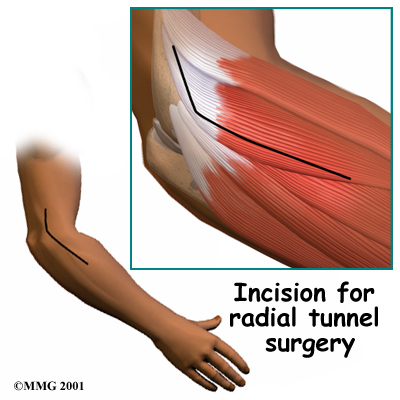

The goal of surgery for radial tunnel syndrome is to relieve any abnormal pressure on the nerve where it passes through the radial tunnel. The surgeon begins by making an incision along the outside of the elbow and down the forearm, near the spot where the radial nerve goes under the supinator muscle.

Soft tissues are gently moved aside so the surgeon can check the places where the radial nerve may be getting squeezed within the radial tunnel. The nerve can be pinched in many spots, so it is important to check all the areas that may be causing problems. Any parts of the tunnel that are pinching the nerve are cut. This expands the tunnel and relieves pressure on the nerve. At the end of the procedure, the skin is stitched together.

The following images show each step: